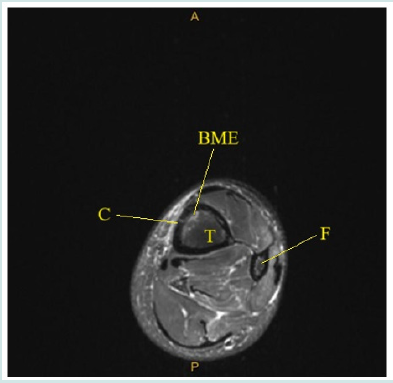

Her 1st MRI, of her ankle, revealed a suspected cortical defect of the tibia with present bone marrow edema. This indicated an incompletely viewed stress fracture of the tibial metadiaphysis, as seen in (Figure 3). For thoroughness another MRI was ordered and received by the patient 3 weeks after the 1st. Her 2nd MRI revealed a near-complete resolution of bone marrow edema, but with a clearly identifiable cortical defect, indicative of a healing stress fracture. This is seen in (Figure 4). The patient was advised to continue her gradual walk-run program through physical therapy after this MRI confirmation. At her 2-month follow-up, the patient reported complete resolution of symptoms.

Figure 3: Axial slice of Magnetic Resonance Imaging (MRI) of left ankle showing cortical irregularity (C) within anterior distal tibial metdiaphysis and mild underlying bone marrow edema (BME) suggestive of potential incompletely imaged stress fracture (SF). Tibia (T) and Fibula (F).